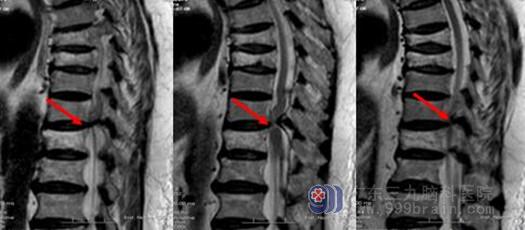

黄韧带骨化核磁